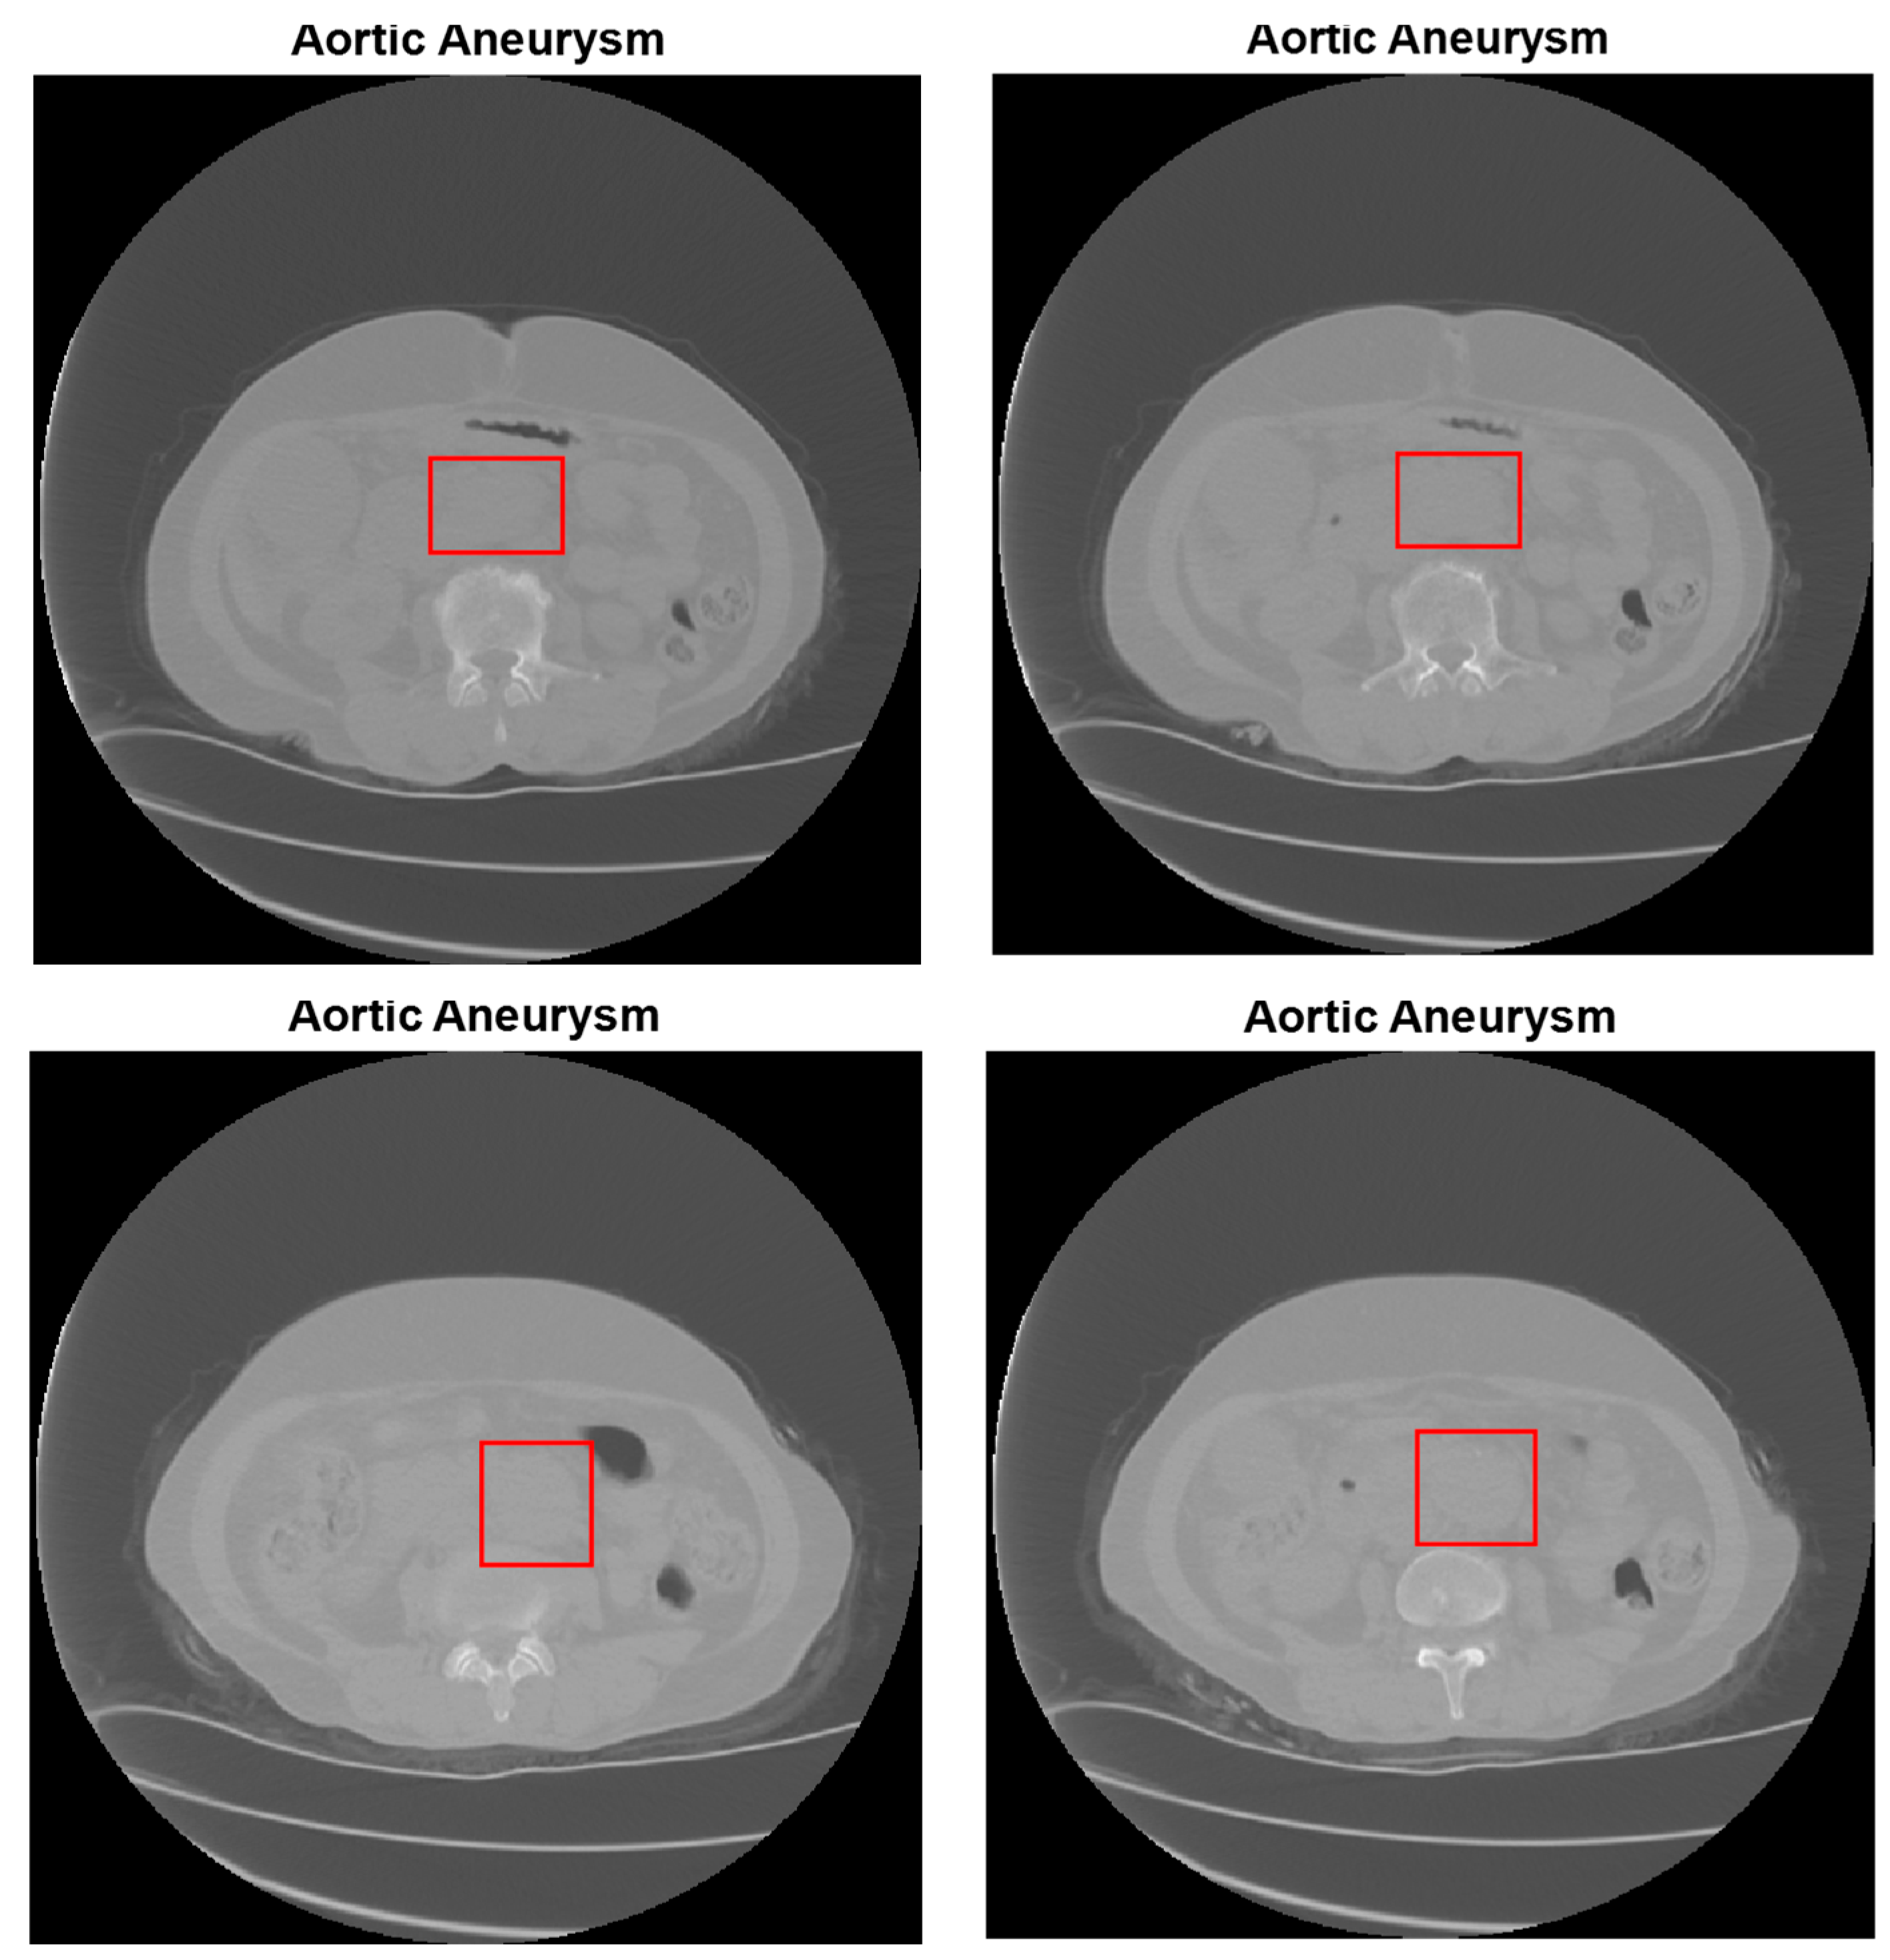

2.2. Abdominal Aortic Aneurysm (AAA) Detection

2.3. Abdominal Aortic Dissection (AAD) Detection